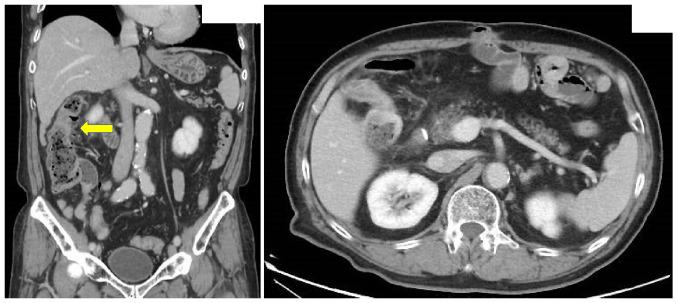

Colorectal metastasis from gastric cancer is rare and may develop several years after gastric cancer surgery. Therefore, colonoscopic findings provide useful diagnostic information. The present report describes a case of gastric cancer colon metastasis diagnosed 8 years and 10 months after gastrectomy for advanced gastric cancer. A 64-year-old male patient underwent gastrectomy in December 2010 and received chemotherapy for 4 years and 10 months after the surgery. Subsequently, the patient was diagnosed as having colorectal cancer by computed tomography in February 2019. Colonoscopy revealed linitis plastica-like colon stenosis; however, biopsy pathology did not reveal any findings indicating malignancy. Right hemicolectomy was performed, and pathological examination revealed colon metastasis from gastric cancer. The patient received chemotherapy but died of peritoneal carcinomatosis 1 year and 8 months after the colectomy. According to literature, colorectal metastasis from gastric cancer is often attributed to hematogenous metastasis and often exhibits characteristic macroscopic features. Treatments, such as chemotherapy for gastric cancer and/or colorectal resection, are considered effective for gastric cancer colorectal metastasis.

胃癌的结直肠转移罕见,且可能在胃癌手术后数年发生。因此,结肠镜检查结果可提供有用的诊断信息。本报告描述了1例进展期胃癌胃切除术后8年10个月被诊断为胃癌结肠转移的病例。一名64岁男性患者于2010年12月接受胃切除术,术后接受了4年10个月的化疗。随后,该患者于2019年2月经计算机断层扫描被诊断为结直肠癌。结肠镜检查显示皮革胃样结肠狭窄;然而,活检病理未发现任何提示恶性肿瘤的迹象。患者接受了右半结肠切除术,病理检查显示为胃癌结肠转移。患者接受了化疗,但在结肠切除术后1年8个月死于腹膜癌。根据文献,胃癌的结直肠转移通常归因于血行转移,且常表现出特征性的宏观特征。对于胃癌结肠转移,诸如胃癌化疗和/或结直肠切除术等治疗方法被认为是有效的。